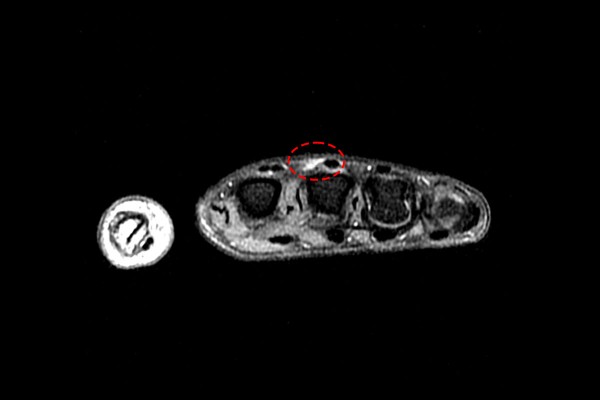

수술 후 MRI를 확인해보면 파열되었던 시상대가 잘 연결된 것이 확인됩니다.

수술 전/후 사진을 비교해보면 더욱 확실하게 잘 봉합된 것이 확인됩니다.